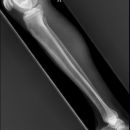

Unterschenkel a.-p. (1. Ebene)

Fraktur, Osteosynthesematerial

Orthograde Darstellung des Kniegelenkspalts, Patella mittelständig. Distaler Unterschenkel mit Darstellung des Sprunggelenkspaltes.

Deckungsgleiche Darstellung der Femurkondylen. Distaler Unterschenkel mit seitlicher Projektion des Sprunggelenkes. Die Fibula projiziert sich in Höhe des Sprunggelenks auf das mittlere bis hintere Drittel der Tibia.